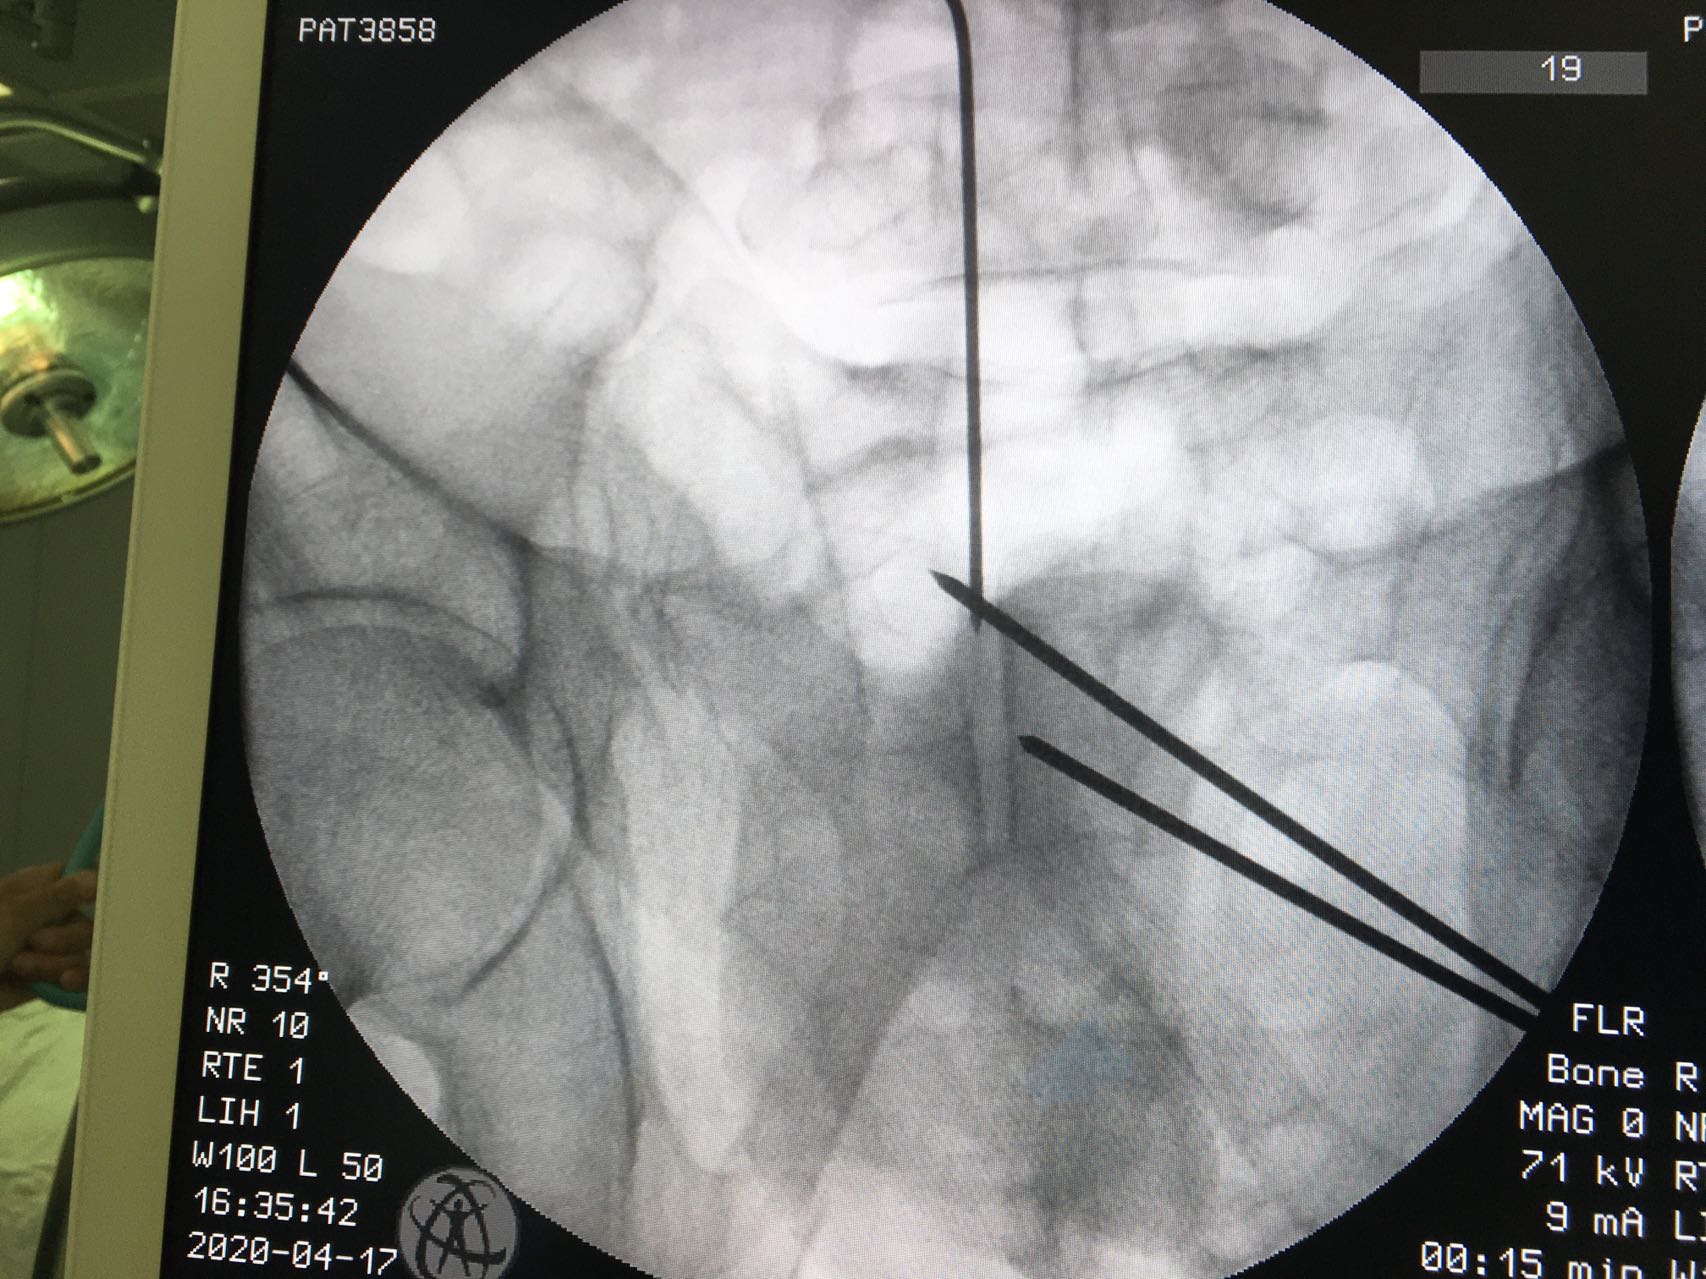

备皮,消毒,摆好透视机器,反复透视,确定最佳的进针点,确定最佳进针方向,一点不能马虎。因为进针的路很窄,旁边也都是重要的人体结构。

骨盆出口位

进针点很好

切7mm皮肤小口,进螺钉。

螺钉位于骨性通道内